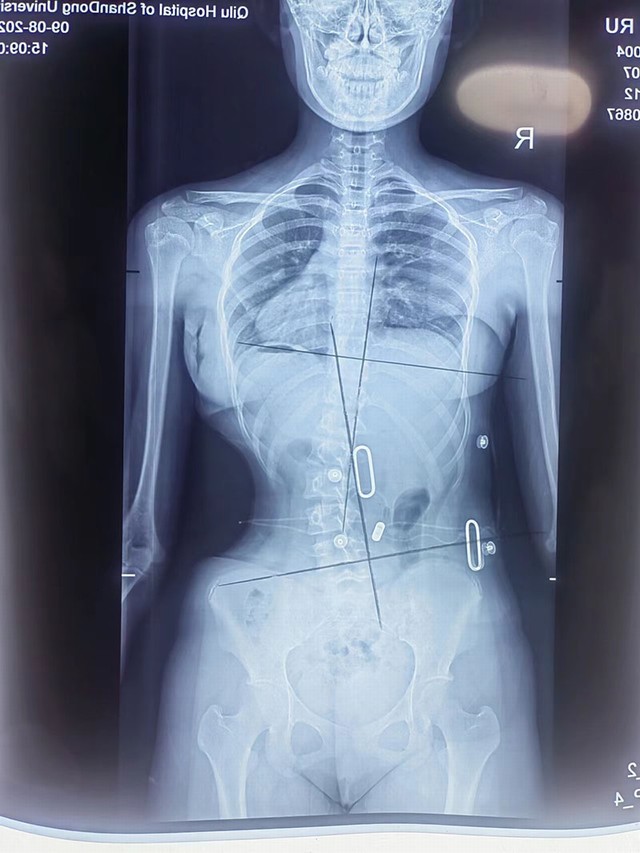

脊柱侧弯矫形器

康复实例